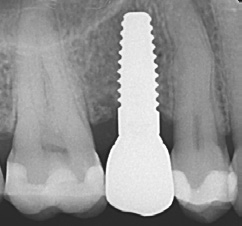

In diesem Fall konnten 2 NobelPearl-Implantate mit je einem Durchmesser von 4,2 mm und der Länge 10 mm für die Implantatpositionen 15 und 25 vorgesehen werden. Die angegebene Länge entspricht dabei dem enossalen Anteil des Implantats. Zu beachten ist, dass zum enossalen Anteil noch ein auslaufend geätzter Halsbereich mit 1,6 mm Höhe hinzukommt, welcher der biologischen Breite Rechnung tragen soll. Folglich weist ein 10-mm-Implantat eine Gesamtlänge von 11,6 mm auf. Die untere Schulter des Profilbohrers entspricht hierbei der enossalen Länge des Implantats ohne den Halsbereich (Abb. 4). Bei einer geringen Mukosadicke kann das Implantat jedoch bis zu 1 mm tiefer platziert werden, sodass nur noch ein Halsbereich von 0,6 mm suprakrestal verbleibt und der enossale Anteil nun 11 mm beträgt.

Die Implantate wurden im Anschluss mit einer ausreichenden Primärstabilität von 30 Ncm und einem suprakrestalen Anteil 0,6 mm platziert. Diese suprakrestale Positionierung wird durch einen gegebenenfalls am Profilbohrer anbringbaren Tiefenstopp (Abb. 7) vereinfacht. Für das Einbringen der Implantate steht ein neues, zur „Inter-X“-Innenverbindung formschlüssiges Eindrehinstrument (Abb. 8) zu Verfügung, wodurch eine optimale Kraftübertragung während des Inserierens des Implantats gewährleistet wird (Abb. 9). Die Einheilkappen sind deutlich abgeflacht und ermöglichen einen einfachen primären Wundverschluss (Abb. 10 und 11). Im vorliegenden Fall verlief die Wundheilung komplikationslos. Nach einer auch für Keramikimplantate heute üblichen Einheilungszeit von 3 Monaten zeigten sich die Implantate in der Röntgenkontrollaufnahme stabil osseointegriert (Abb. 12). Es fanden sich an beiden Implantat-Loci entzündungsfreie Weichgewebsverhältnisse, woraufhin mit der prothetischen Versorgung des Implantats begonnen werden konnte.